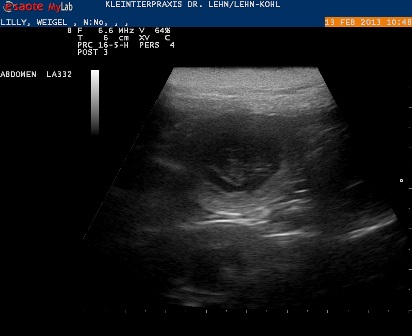

13.02.2013 - 28. Tag

Lilli ist trächtig :) es ist sooo wunderbar!

Wir konnten Herzchen schlagen sehen und haben eine Fruchthülle vermessen:

Welpe mit Fruchthülle hatte heute einen Duchmesser von ca. 2,4 cm.

D.h. die Befruchtung hat zeitnah mit dem Decken geklappt.

Das erste Foto von unseren G's:

In der Mitte sehr ihr schön eine Fruchtblase mit dem Kleinen drin,

rundherum öffnen sich auf diesem Bild schemenhaft die nächsten Fruchtblasen :)